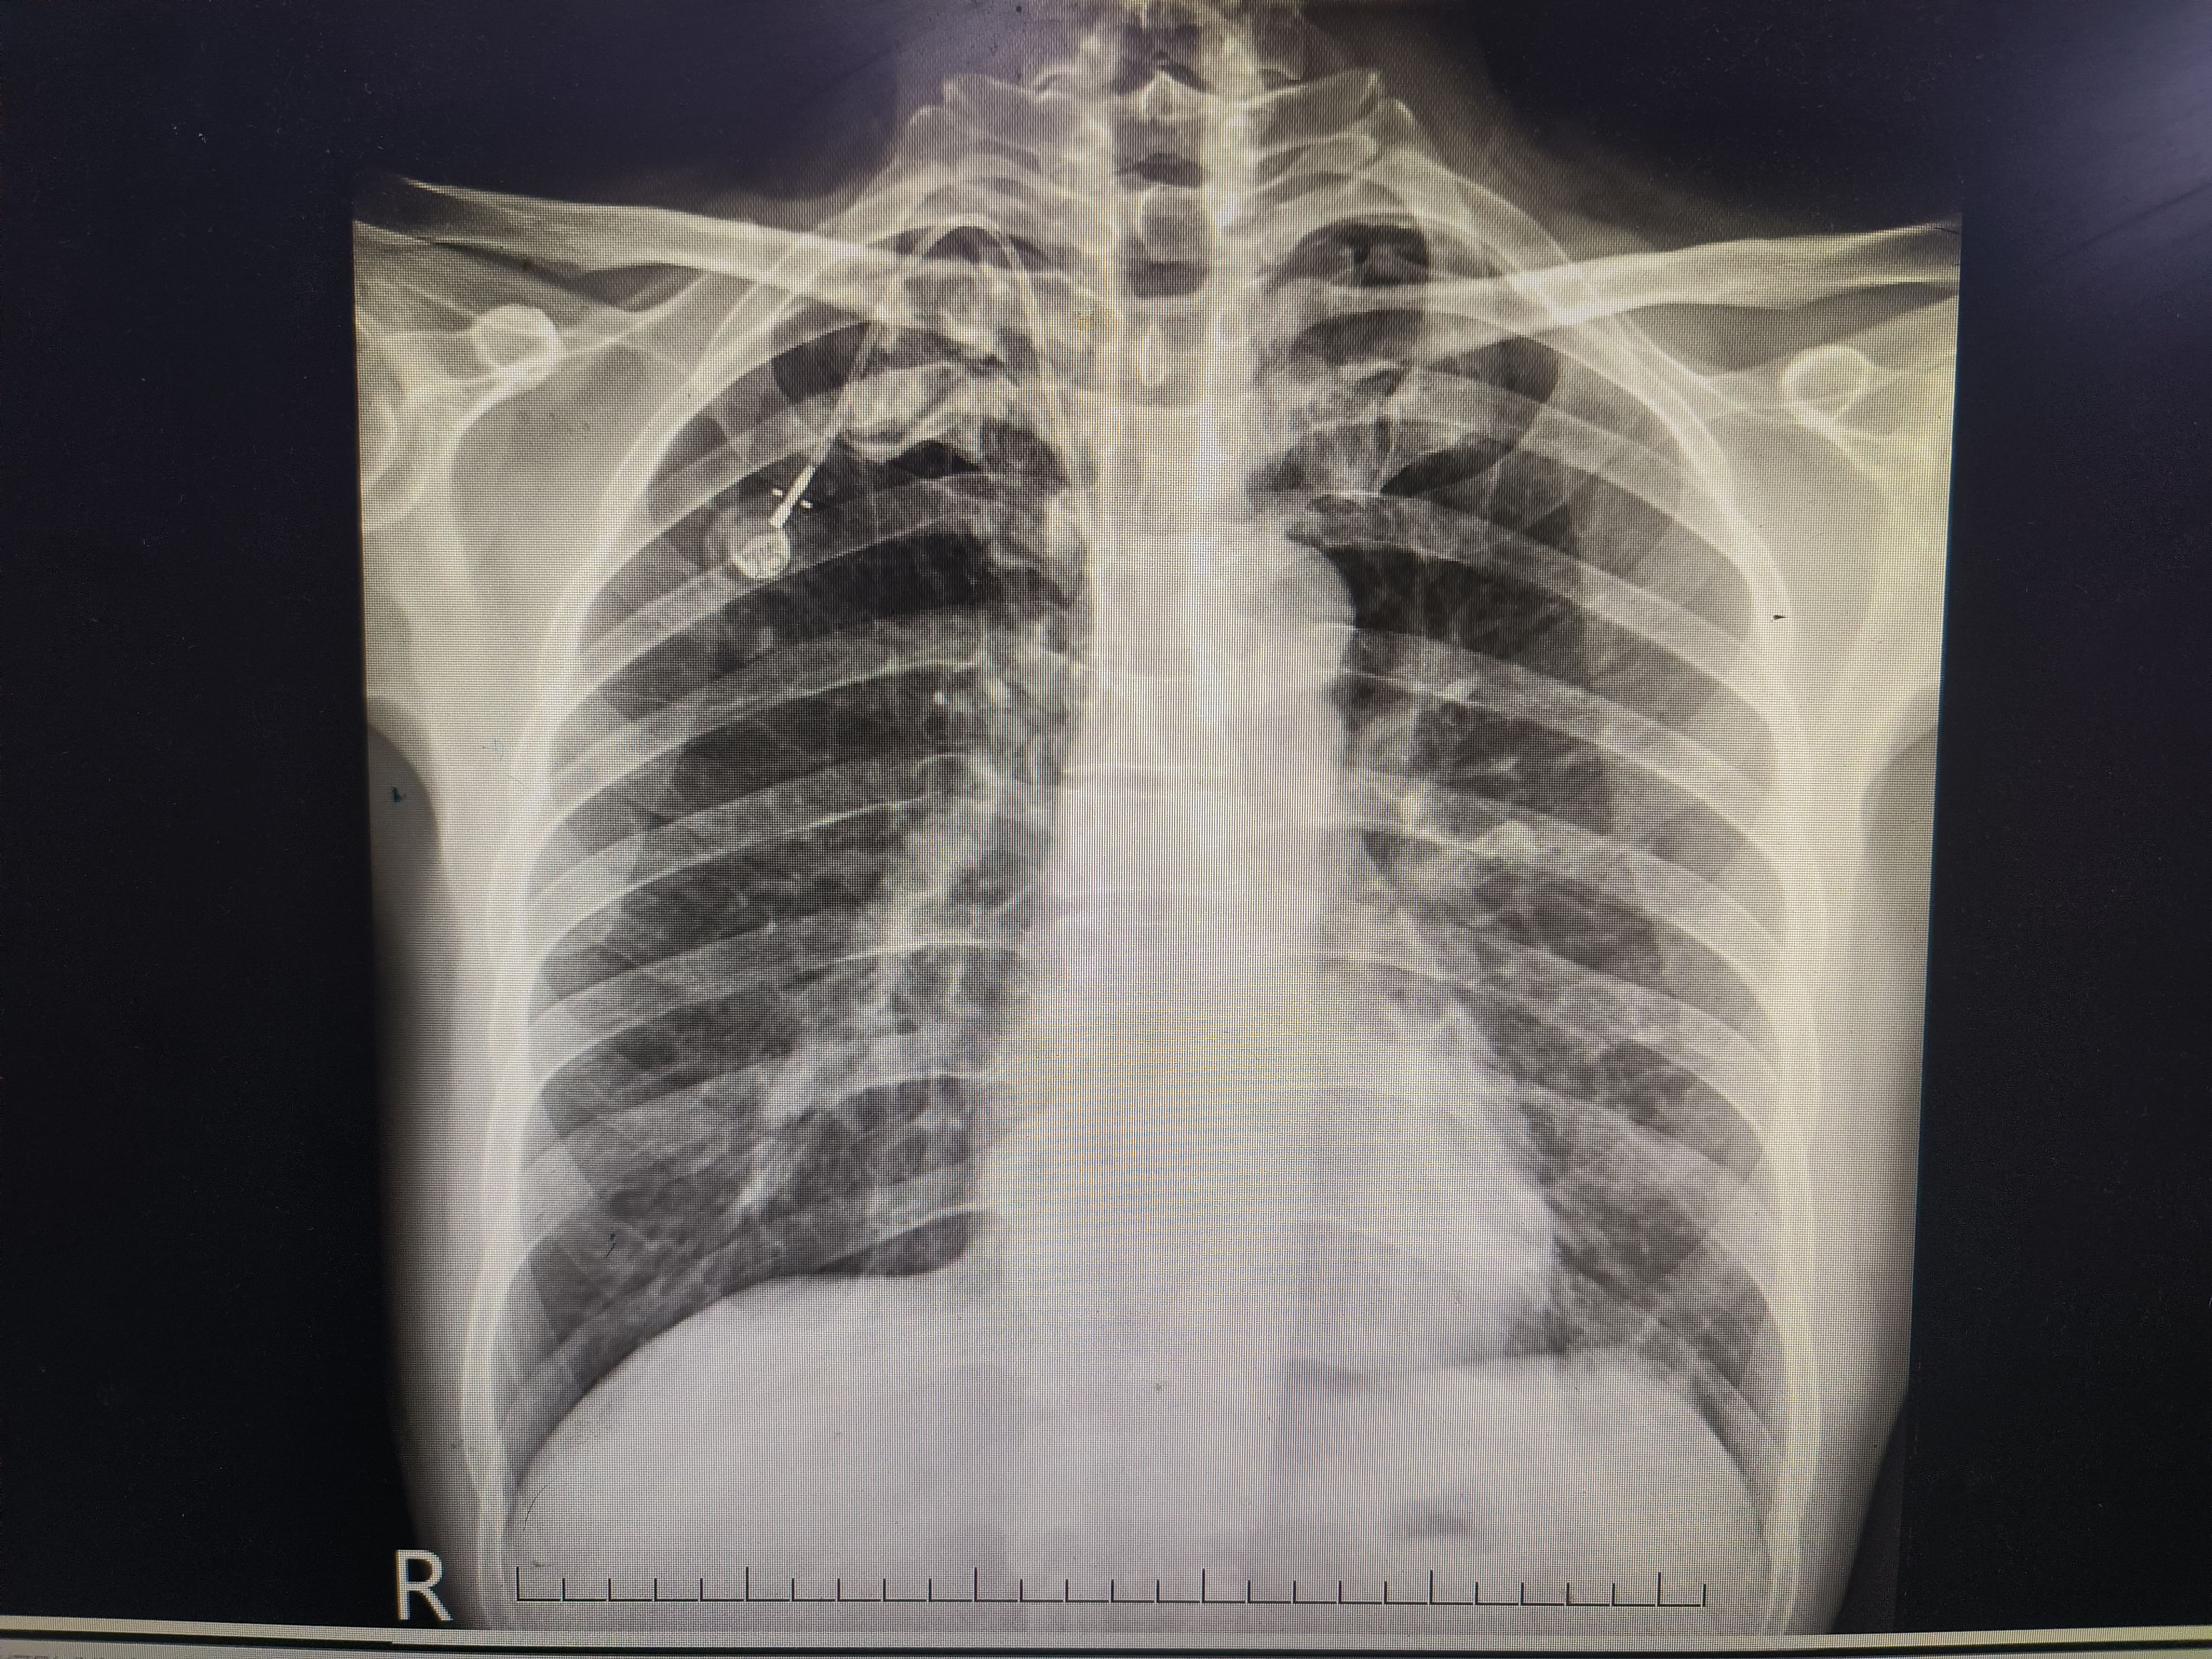

肝癌患者,上腔静脉阻塞合并颈部和上肢血管多处血栓,急需解决化疗输液难题,右侧曾有腹股沟斜疝,尝试左侧腹股沟入路,输液港底座置于左下腹壁,手术顺利,希望接下来的治疗能帮你跑赢时间✊🏻✊🏻